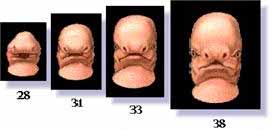

This picture shows a fetus on the

35th day (Not shown - Ed.), which does not take a human

form. And the following picture, shows the same fetus on the

42nd day. So far. Dr. Persaud says, we cannot discern a human shape. We see this illustrative picture, made by

CIBA, depicting the fetus on the 42nd day (See Fig 7.1). One week later, during the seventh week, immediately after 42 days, the picture is completely changed as we see here (See Fig. 7.2).

The prophetic hadeeth in this respect says: This picture shows a fetus on the

35th day (Not shown - Ed.), which does not take a human

form. And the following picture, shows the same fetus on the

42nd day. So far. Dr. Persaud says, we cannot discern a human shape. We see this illustrative picture, made by

CIBA, depicting the fetus on the 42nd day (See Fig 7.1). One week later, during the seventh week, immediately after 42 days, the picture is completely changed as we see here (See Fig. 7.2).

Fig. 7.1

Fig. 7.2